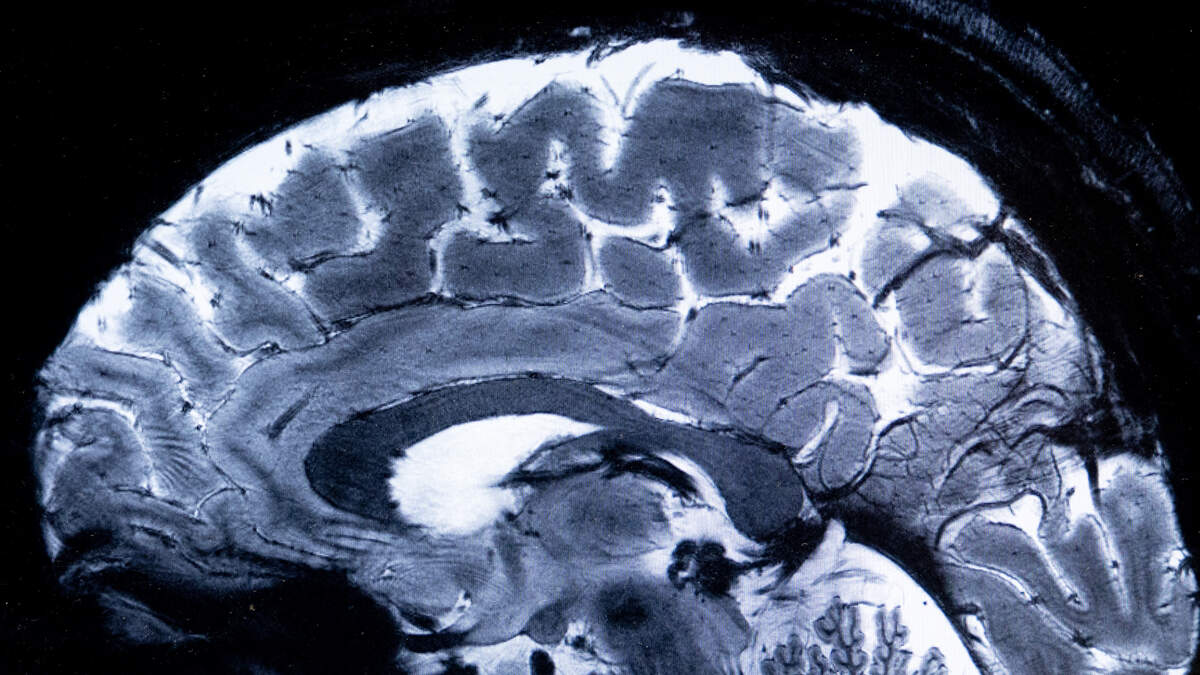

(Boca Raton, FL) - Florida Atlantic University's NeuroInnovate Center is the first in the world to combine MRI and ultrasound technologies.

FAU researchers say the breakthrough speeds up non-invasive treatment for disorders such as Alzheimer’s and Parkinson’s disease.

According to FAU: The addition of a low-frequency focused ultrasound unit (Insightec Prime 220 V3) creates a unified environment that supports everything from preclinical investigations to FDA-regulated clinical trials and patient care. The integration of the NordicNeuroLab fMRI system, in-scanner EEG, and Biopac physiological monitoring tools will give students, residents and faculty unmatched exposure to emerging research and clinical tools.